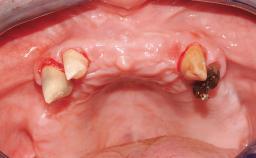

Transition from an “irrational to treat” Maxillary Dentition to a Full-Arch Segmented FDP by Early Loading of Eight Implants Placed Using the Staged Approach

The staged approach permits the transition from an “irrational to treat”dentition to a full arch implant supported restoration without any need to use a removable provisional prosthesis or to apply the immediate-placement and immediate-loading techniques. A failing dentition is the usual indication for a staged treatment. On the other hand, the dentition should still contain many residual teeth, but with few or none of them being suitable for use as definitive abutments for a full-arch fixed restoration.This situation is usually the result of advanced periodontal disease or of the failure of an extensive fixed prosthesis.